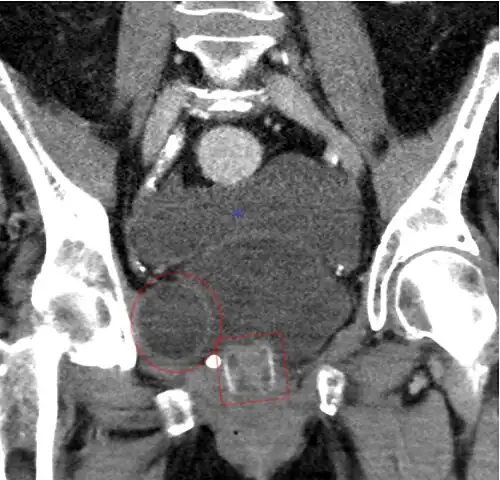

Artificial urinary sphincter

Another procedure to treat incontinence is the use of an artificial urinary sphincter, more used in men than in women. In this procedure, the surgeon enters and wraps the cuff of the artificial urinary sphincter around the urethra, in the same manner a blood pressure cuff wraps around your arm. The device includes a pump implanted under the skin that, when pressed by the patient, loosens the cuff, allowing for free urination. After that, the artificial sphincter automatically regains its pressure, closing the urethra again, and providing proper continence.[20]

CT scan of an artificial urethral sphincter in a woman -